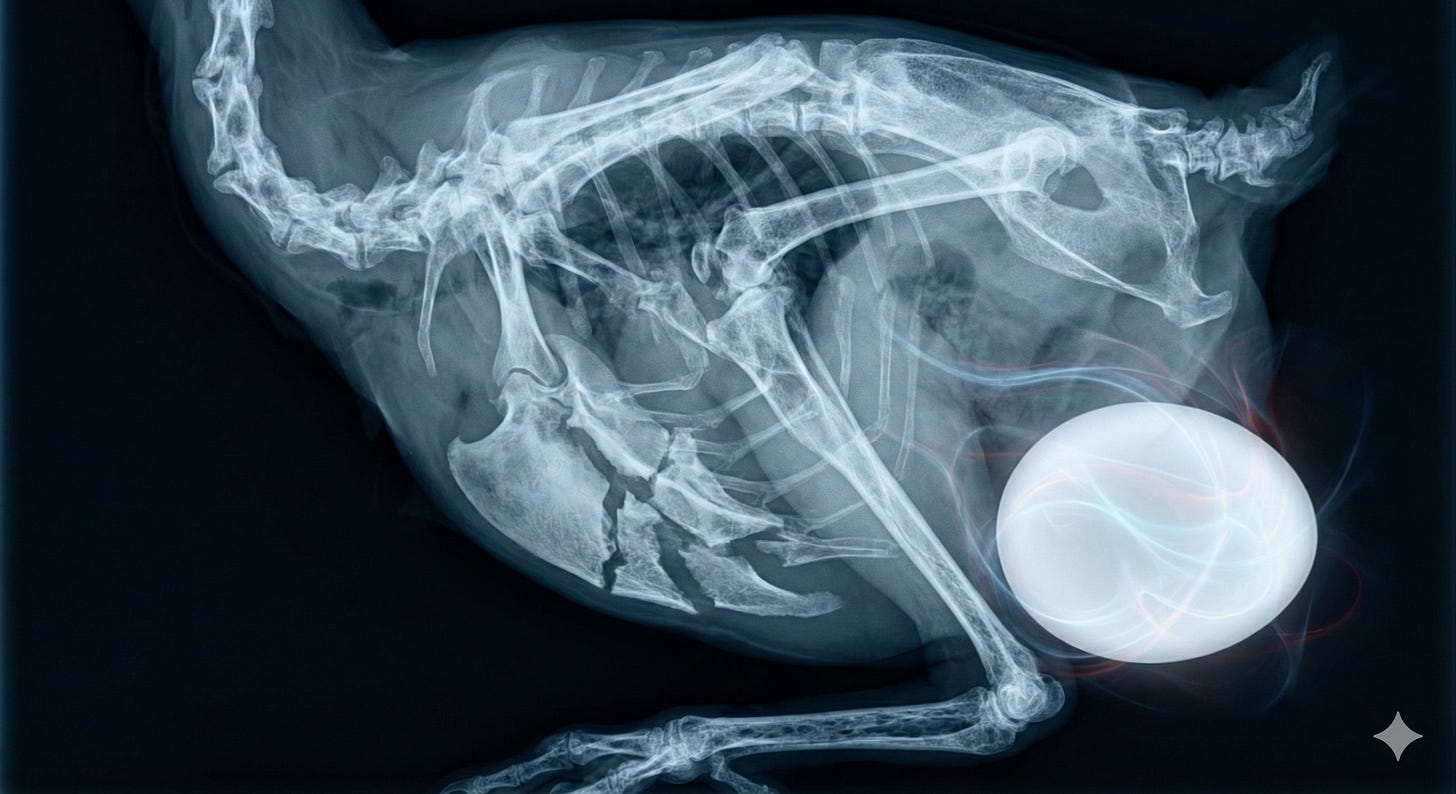

Millionen Hühner leiden an Aszites (Bauchwassersucht). Da das Herz-Kreislauf-System den gigantischen Sauerstoffbedarf der künstlich aufgeblähten Muskelberge nicht decken kann, steigt der Blutdruck in den Lungenarterien, Flüssigkeit tritt aus und füllt den Bauchraum, bis die Tiere buchstäblich von innen ertrinken.